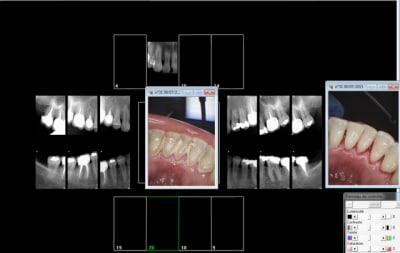

Le problème c'est que quand ca merde un sealant c'est qu' aucune radio n'a été effectuée préalablement et que la carie sous jacente continue à évoluer ou que ca fait chier de faire anesthésie + soin une face alors que c'est à peine plus rémunéré ( soin une face sur enfant 22,31 et sealant 21,69)

Sans digue avec optragate + linguafix tu peu meme prendre des photos sans etre dans la salive (avec les 2 mains de libre) et t'apercevoir une fois avoir passé le polissage d'avoir oublié un demi millimètre de sillon -))))